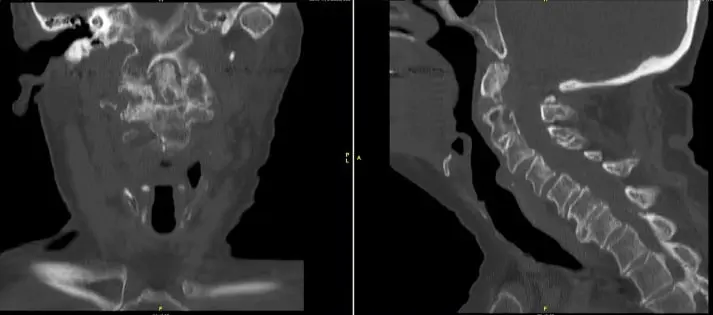

He was having balance issues along with weakness in all 4 extremities. X rays, CT scan and MRI showed a non-union of odontoid fracture with pannus formation and fibrous union, instability with compression of spinal cord at C1-2 level.